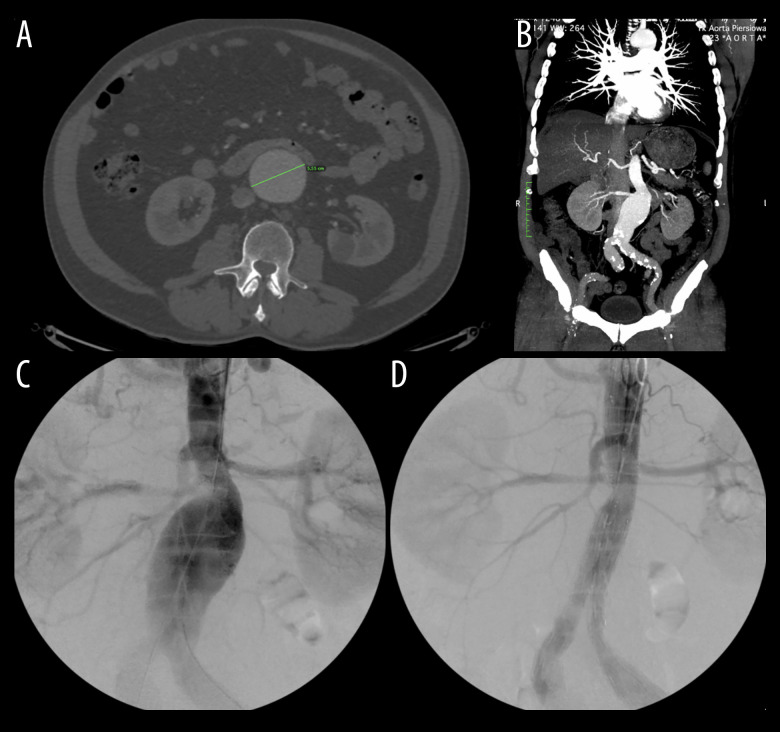

主动脉-十二指肠瘘(ADF)是主动脉和十二指肠之间的交通,需要紧急主动脉修复。然而,它经常导致危及生命的并发症。因此,早期和适当的诊断方法是必要的,以提供充分的治疗。本报告描述了一名68岁男性患者,在使用口腔造影计算机断层扫描(CT)对14厘米腹主动脉瘤(AAA)进行紧急血管内修复后出现肛肠-十二指肠瘘的病例,并讨论了延迟治疗和ADF管理的后果。我们报告一例68岁白人男性腹部腹胀,经进一步检查诊断为AAA,并通过血管内动脉瘤修复(EVAR)成功治疗。然而,1年后,发现了一个漏洞,尽管医生的努力,但由于患者连续数年推迟治疗,整体治疗变得复杂。动脉瘤继续扩大,直到达到14厘米。尽管血管内瘘成功修复,但通过CT和口腔造影诊断为十二指肠主动脉瘘(DAF)。患者保守处理动脉瘤囊引流和抗生素治疗,减少了动脉瘤囊的大小。尽管进行了早期诊断和干预,但由于进一步的并发症,患者的病情恶化,最终导致死亡。结论:本病例报告表明,在其他方法无法检测DAF的情况下,CT联合口腔造影在检测DAF方面具有潜在的有用诊断作用,并强调了及时干预以预防危及生命的并发症的重要性。然而,需要进一步的研究来探索潜在的机制及其可复制性。

BACKGROUND Aorto-duodenal fistula (ADF) is a communication between the aorta and the duodenum and requires urgent aortic repair. However, it often leads to life-threatening complications. Thus, an early and appropriate diagnostic method is necessary to deliver adequate treatment. This report describes the case of a 68-year-old man with anaorto-duodenal fistula following emergency endovascular repair of a 14-cm abdominal aortic aneurysm (AAA) identified using oral contrast computed tomography (CT), and discusses the consequences of delayed treatment and ADF management. CASE REPORT We present a case of a 68-year-old White man with abdominal bloating, who upon further examination was diagnosed with an AAA, which was successfully treated by endovascular aneurysm repair (EVAR). However, 1 year later, an endoleak was discovered and, despite the physicians' efforts, the overall treatment was complicated due to the patient's continuous postponement of treatment over several years. The aneurysm continued to expand until it reached 14 cm. Despite the successful endovascular repair of the endoleak, a duodeno-aortic fistula (DAF) was diagnosed using CT with oral contrast. The patient was managed conservatively with aneurysmal sac drainage and antibiotic therapy, which decreased the size of the aneurysmal sac. Despite early diagnostic efforts and interventions, the patient's condition deteriorated due to further complications, ultimately resulting in death. CONCLUSIONS This case report demonstrates a potential useful diagnostic role of CT with oral contrast in detecting DAF, in situations when other methods fail to do so, and emphasizes the importance of prompt intervention to prevent life-threatening complications. However, further investigations to explore the underlying mechanism and its replicability are required.